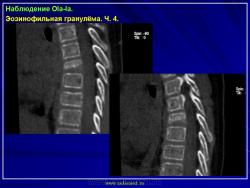

Тело позвонка является наиболее часто поражающейся частью позвоночника. Ранние поражения проявляются, как литические очаги.

Формируется «VERTEBRA PLANA», что может привести к боли и значительным неврологическим расстройствам.